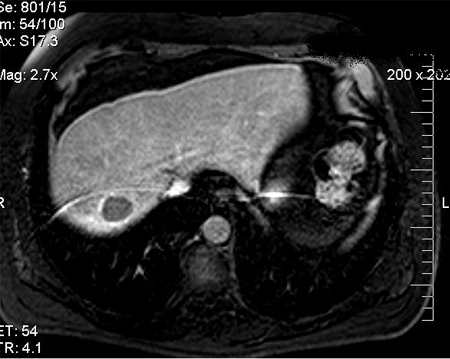

MRI: following transarterial chemoembolization treatment

From the personal collection of Badar Muneer MD, Florida Hospital Transplant Center, Orlando, FL; used with permission